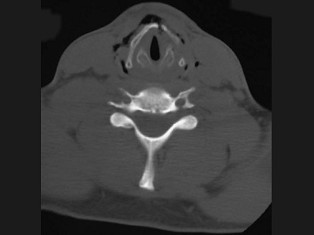

11.27岁男性,开车外出在高速行驶时翻车,呼吸困难,喉部肿胀,CT检查如图所示,请选择正确的描述或诊断 ( )![]() ![]() ![]() ![]() |

| 正确答案:ABCE |